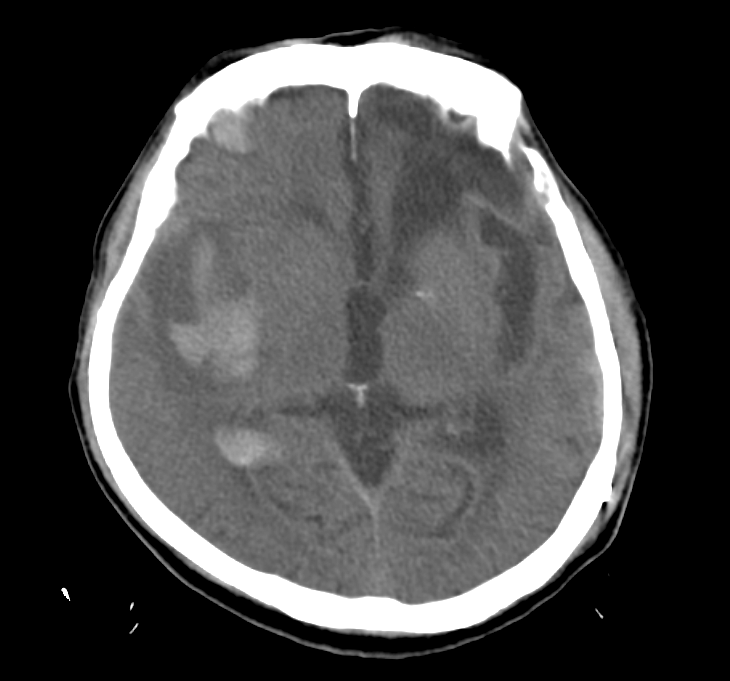

- CT: to quickly check for bleeding in the brain